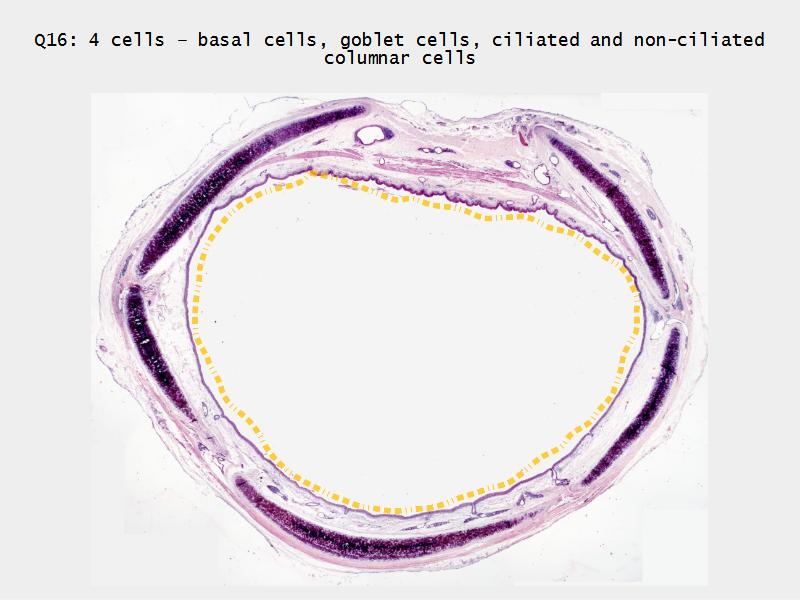

Respiratory epithelium

- Pseudostratified

- Ciliated

- Columnar

- Epithelium with

- 4 Cells

- Ciliated columnar cells

- Non-ciliated columnar cells

- Goblet cells

- Basal cells

Trachea